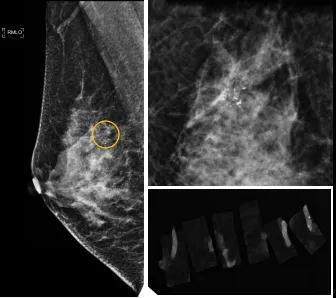

46歲的某女士在西安國際醫(yī)學(xué)中心醫(yī)院體檢時,行乳腺X線攝影(俗稱鉬靶)發(fā)現(xiàn)右乳可疑簇狀鈣化,分布范圍不到1厘米,臨床觸不到,超聲很難發(fā)現(xiàn),但是這種鈣化風(fēng)險(xiǎn)比較高,依據(jù)國際BI-RADS指南需要明確病理!

西安國際醫(yī)學(xué)中心醫(yī)院影像診療中心陳寶瑩副主任帶領(lǐng)的團(tuán)隊(duì),采用全數(shù)字化乳腺X線三維立體定位系統(tǒng)可實(shí)施。這個團(tuán)隊(duì)的成員大部分來自知名三甲醫(yī)院,有著十余年影像引導(dǎo)下乳腺介入診療的經(jīng)驗(yàn),X線引導(dǎo)穿刺定位和活檢例數(shù)居西北前列。為減少患者創(chuàng)傷,在詳細(xì)判讀了患者資料,并與患者及甲乳外科劉曉敏主任充分溝通的基礎(chǔ)上,團(tuán)隊(duì)確定采用全數(shù)字化乳腺X線三維立體定位系統(tǒng)下實(shí)施粗針活檢。

當(dāng)天,乳腺X線三維立體定位系統(tǒng)清晰顯示出了所有鈣化。為了獲取充足的組織量,保證病理診斷的準(zhǔn)確性,團(tuán)隊(duì)選用14G穿刺針并多點(diǎn)、多角度取材,組織取出后,又立即在高清標(biāo)本攝影系統(tǒng)中進(jìn)行投照,從而確定了取出組織中具有足夠的可疑鈣化。整個過程患者無任何不適,活檢結(jié)束后即回家觀察。